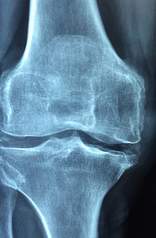

무릎 통증 원인에 대해 자세히 알아보도록 하겠습니다. 무릎 관절은 우리 몸의 중요한 부분으로, 우리의 움직임을 지원하고, 충격을 흡수하고, 균형을 유지하는 역할을 합니다. 하지만 무릎 관절은 나이가 들면서 퇴행성 관절염이라는 질환에 걸릴 가능성이 높아지는데요, 이는 관절의 연골이 마모되어 통증과 염증, 운동장애를 일으키는 병입니다.

- 관절염 : 무릎 관절에 염증이 생기는 질환입니다. 염증은 관절의 손상, 감염, 면역 반응 등에 의해 발생할 수 있습니다. 일반적으로 무릎 염증 증상은 다음과 같습니다. 무릎을 움직일 때 무릎뼈에서 소리가 난다, 비가 오는 날 무릎 통증이 심해진다, 무릎이 뻣뻣해서 움직일 때 불편하다, 무릎 부위가 붓는다, 무릎 관절이 약해서 걷거나 서있을 때 종종 무릎이 구부러짐.

- 골다공증 : 골다공증은 뼈가 약해지고 쉽게 부러지는 질환입니다. 골다공증은 나이가 들면서 뼈의 밀도가 감소하면서 발생할 수 있습니다. 골다공증은 무릎뿐만 아니라 다른 부위의 뼈도 영향을 줄 수 있습니다. 골다공증의 증상은 다음과 같습니다. 무릎 관절에 통증이 생김, 무릎뼈가 쉽게 부러짐, 신장이 줄어듦, 자세가 굽어짐.